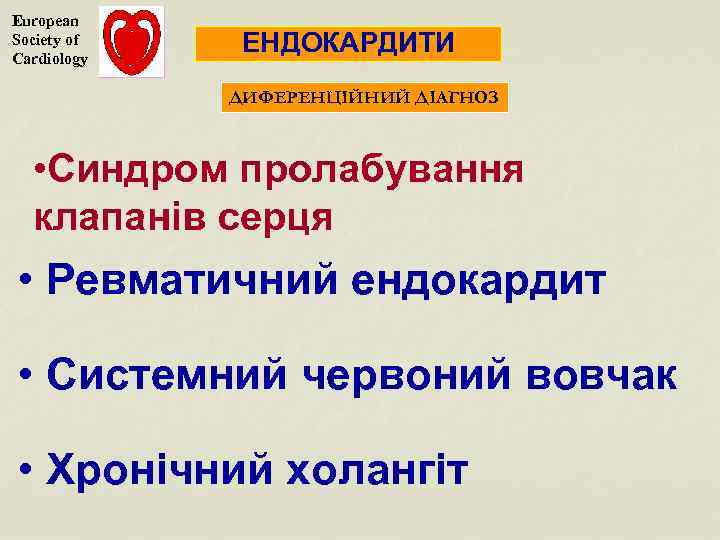

European Society of Cardiology ЕНДОКАРДИТИ ДИФЕРЕНЦІЙНИЙ ДІАГНОЗ • Синдром пролабування клапанів серця • Ревматичний ендокардит • Системний червоний вовчак • Хронічний холангіт